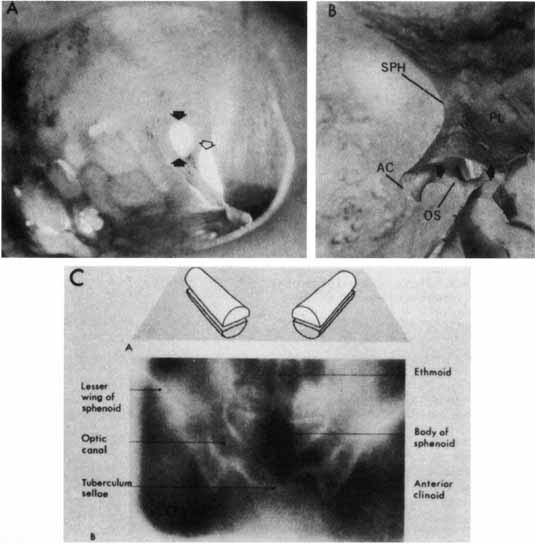

The optic canal runs posteromedially in the spheroid bone, at an angle of approximately 35° with the midsagittal plane (Fig. 5). The optic canal is 4 to 10 mm in length and contains not only the optic nerve but also the ophthalmic artery, branches of the carotid sympathetic plexus, and extensions of the intracranial meninges that form the sheaths of the optic nerve. The aural covering of the nerve and the periosteum of the canal are fused, but the arachnoid is continuous, permitting the subarachnoid space of the optic nerves to communicate freely with the intracranial subarachnoid space, both of which contain cerebrospinal fluid.

Fig. 5 The optic canal. A. Anterior view of left orbital apex. Orbital end of optic canal is vertically oval (black arrows) and separated from superior orbital fissure (open arrow) by optic strut. Note transilluminated ethmoidal and sphenoidal air cells, which form medial orbital wall and medial wall of optic canal. B. Posterior view of intracranial aspect of left optic canal demonstrating horizontally oval contour. The optic strut (OS) forms the ventrolateral margin of the canal and separates it from the carotid artery. In this preparation the ethmoidal and sphenoidal air cells have been opened. AC, anterior clinoid; PL, planum; SPH, sphenoidal wing. C. Tomographic section of optic canals in upper diagram. Normal axial tomogram below. (Illustration C from Harwood-Nash DC: Optic gliomas and pediatric neuroradiology. Radiol Clin North Am 10:83, 1972)